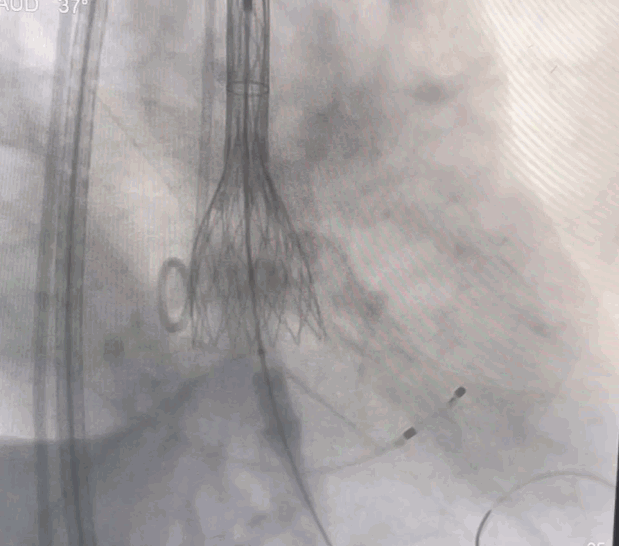

术中操作

经右侧颈动脉途径,直头导丝跨瓣成功后送入猪尾导管至左室,置入22F动脉鞘管。结合术前CT,装配好VitaFlow Liberty™27号瓣膜,在加硬导丝支撑下,送导管输送系统至主动脉根部并跨过主动脉瓣口,主动脉根部造影,确认瓣膜处于理想位置,在起搏下,经过慢释放、快释放及终释放,完成瓣膜释放过程。术后病人生命体征平稳,跨瓣压差明显改善,无瓣周漏。

球囊预扩

瓣膜释放完成

瓣膜形态良好,无瓣周漏